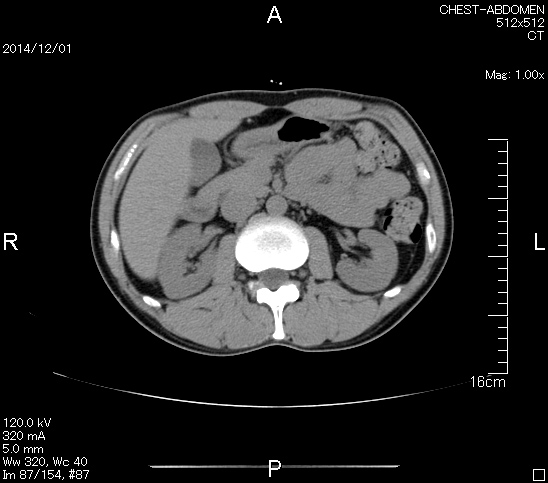

マーカー、CT画像、問題なし!!

血液検査結果もほとんど文句なしの正常値。